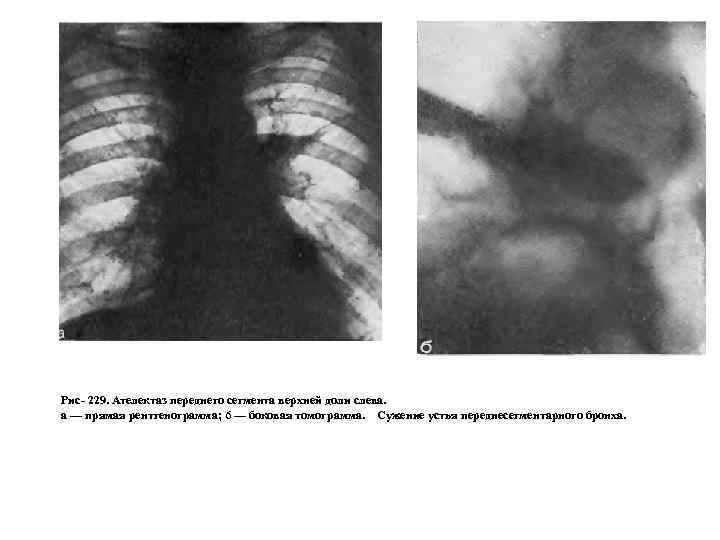

Применение функциональных проб позволяет заметить смещение средостения в фазе выдоха в противоположную сторону. Анализ легочного рисунка в этой фазе показывает, что соответственно пораженным участкам заметно обеднение сосудистого рисунка из за веерообразного раздвигания сосудистых ветвей и уменьшения кровенаполнения, вследствие повышенного внутриальвеолярного давления. По мере роста опухоли наступает четвертая фаза. Последняя связана с полным перекрытием просвета бронха, чему способствует скопление в нем слизи, мокроты и крови. Все эти факторы рано или поздно приводят к III стадии нарушения бронхиальной проходимости, к возникновению ателектаза (рис. 229). Именно сложный характер пробки, обтурирующей бронх, является одной из причин так называемых перемежающихся ателектазов. Стадия ателектаза обычно диагностируется при поражении зональных и долевых бронхов и реже при сегментарных. Сегментарные поражения часто расцениваются как проявления пневмонии, и лишь тогда, когда развивается ателектаз зоны или доли, устанавливается диагноз рака легкого. Описанные фазы нарушения бронхиальной проходимости от гиповентиляции через клапанное вздутие к ателектазу также последовательно наступают и при развитии опухоли в зональных долевых и главных бронхах.

Рис 229. Ателектаз переднего сегмента верхней доли слева. а — прямая рентгенограмма; 6 — боковая томограмма. Сужение устья переднесегментарного бронха.